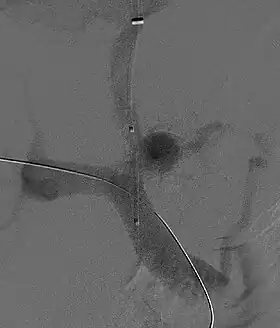

_in_progress.jpg.webp)

A transjugular intrahepatic portosystemic shunt (TIPS) involves the decompression of the high pressures in the portal circulation by placing a small stent between a portal and hepatic vein. This is done through radiologically guided catheters which are passed into the hepatic vein either through the internal jugular vein or the femoral vein. Theoretically, a decrease in portal pressures is thought to reverse the hemodynamic phenomena that ultimately lead to the development of hepatorenal syndrome. TIPS has been shown to improve kidney function in patients with hepatorenal syndrome.[8][38][39] Complications of TIPS for treatment of HRS include the worsening of hepatic encephalopathy (as the procedure involves the forced creation of a porto-systemic shunt, effectively bypassing the ability of the liver to clear toxins), inability to achieve adequate reduction in portal pressure, and bleeding.[8][38]